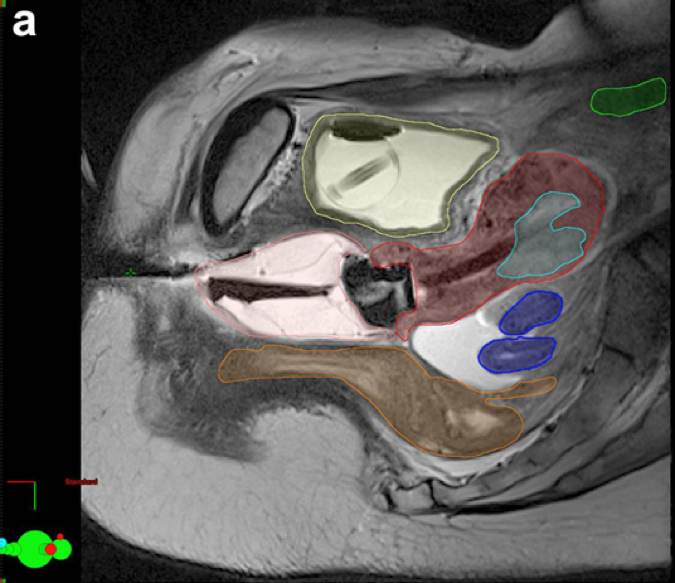

Primär intrauterin brachyterapi

Intrauterin brachyterapi är ett alternativ till kirurgi för patienter i kliniskt stadium I–II med hög operationsrisk till följd av samsjuklighet. Behandlingen anses vara kurativ i 70–80 % av fallen 153 154 155 .

Dosplanering bör ske med hjälp av DT- eller MRT-bilder tagna med applikatorerna på plats. HR-CTV inritas som hela uterusvolymen. Enligt rekommendationer från GEC ESTRO 156 kan HDR-brachyterapi ges med dosen 6 x 7 Gy till HR-CTV. Enligt Clinical Practice Guidelines in Oncologys (NCCN) rekommendationer bör patienten få en total dos (EQD2) > 48 Gy till uterus, cervix och 1–2 cm av vagina när endast brachyterapi används 157 .

Figur 8. Contouring for medically inoperable endometrial cancer using intraoperative magnetic resonance imaging (MRI) or computer tomography (CT). (a) Sagittal slices of T2-weighted MRI showing gross tumor volume (light blue) and clinical target volume including uterus, cervix, and upper vagina (red) with adjacent sigmoid colon (dark blue), rectum (orange), bowel (green), and bladder (yellow) 157 .